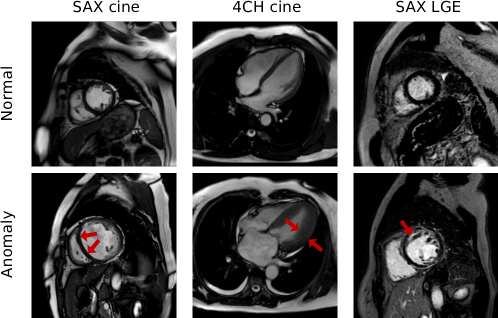

Cardiac Magnetic Resonance (CMR) imaging provides comprehensive myocardial functional and tissue characterization through multiparametric protocols, making it a diagnostic gold standard for cardiomyopathy evaluation [1]. Routine protocols include short-axis (SAX) and 4-chamber (4CH) cine CMR sequences for quantitative cardiac motion analysis, as well as SAX Late Gadolinium-Enhanced (LGE) sequences for identifying myocardial fibrosis and scar tissue (Fig. 1). Despite the diagnostic superiority of CMR, its clinical implementation is limited by (1) time-consuming cross-sequence analysis with observer variability and (2) restricted gadolinium (Gd) use in patients with renal impairment or pregnancy. These barriers hinder its scalability for population-level screening, highlighting the necessity of developing an automated, non-contrast CMR-based cardiomyopathy screening model.

Refer to caption

Figure 1: Typical CMR findings in cardiomyopathy patients across different sequences, such as abnormal ventricular dilation (left), abnormal ventricular hypertrophy (middle), and abnormal hyperintense regions in myocardial tissue (right).